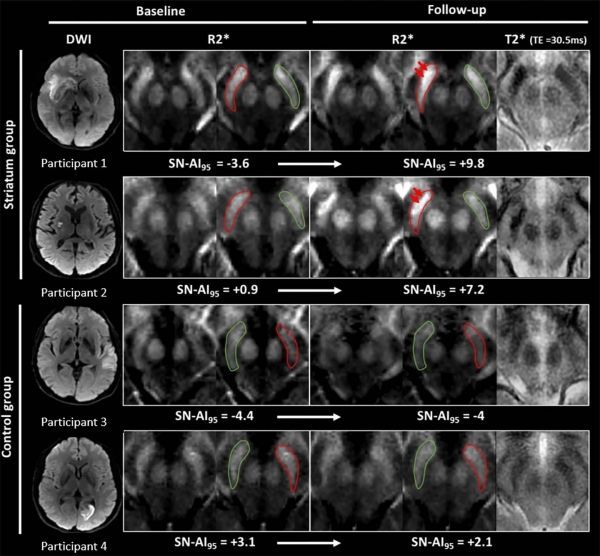

Image: Images show illustrative examples of visual R2? modifications within substantia nigra (SN) at baseline (24-72 h) and follow-up (1 y) in striatum (participants 1 and 2) and control groups (participants 3 and 4). (Credit: Radiological Society of North America)